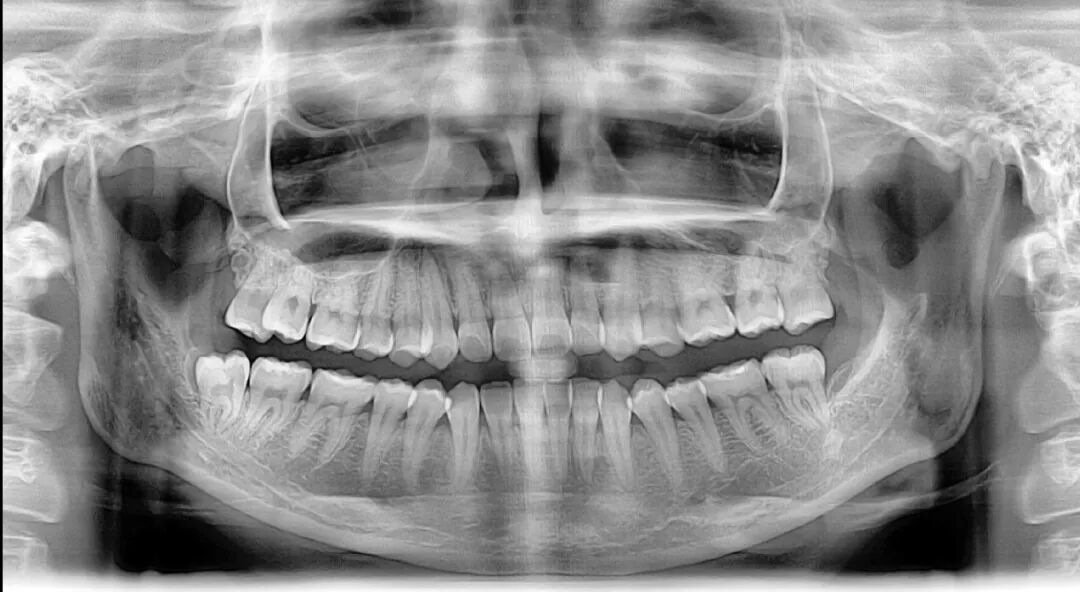

矫正前,拍摄牙齿全景片和头颅侧位X光片是必不可少的一步 | www.lovelytooth.com

接下来,我拍摄了曲面断层和投影侧位片以及全口牙齿锥形束CT,用于描绘标志点进行线角的测量,最后用3D扫描仪记录了牙齿的全貌,牙齿矫正的全面设计不仅包括表面上的牙齿排列、侧面像的协调,而且还要深入到骨骼结构、发育潜能、动静态的颌位关系。